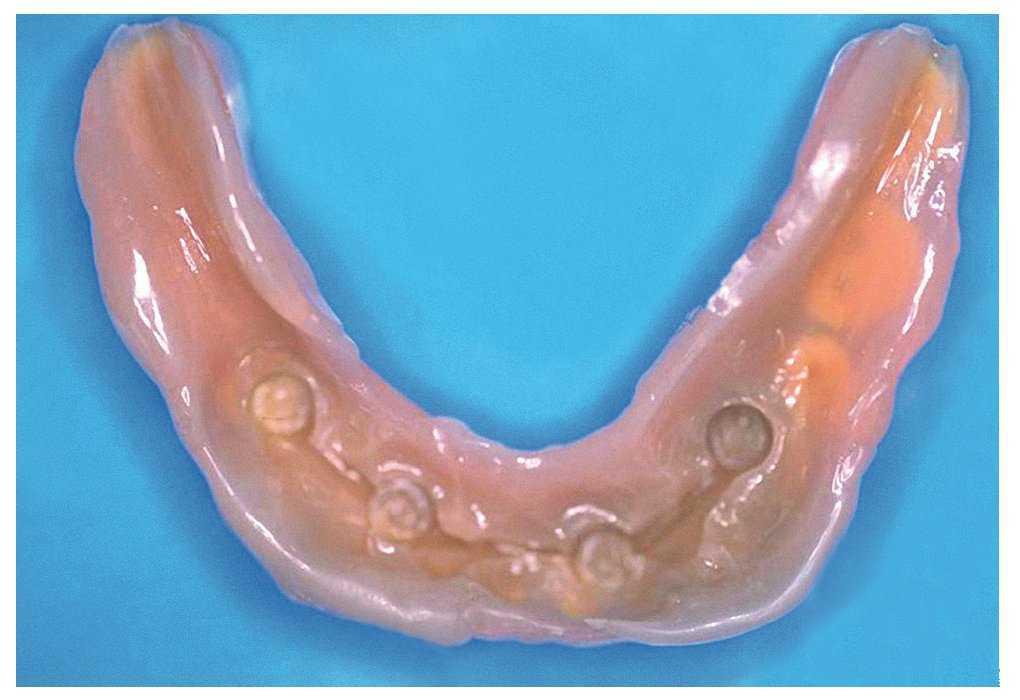

Los mini implantes BEGO cuentan con un diseño biónico para poder garantizar una elevada resistencia a la fatiga a pesar de su diámetro reducido (fig. 9). También se dispone de unas barras prefabricadas de una aleación de metales no preciosos que se pueden combinar con estos implantes (Wirobond, BEGO). La aleación es resistente a la corrosión, electroquímicamente estable y ofrece una resistencia mecánica muy elevada9. Una vez cortadas a medida, las piezas prefabricadas se sueldan por láser y forman una estructura de barras delgada y altamente resistente. Gracias a la ferulización y a la elevada estabilidad primarias, estos mini implantes también son adecuados para la carga inmediata según el principio de Ledermann (fig. 10). El concepto de amortiguación de la carga («soft loading») «limburguesa» constituye una variante de la carga inmediata. Esta técnica se utiliza cuando ha sido necesario expandir el hueso en mayor medida, como en casos con crestas alveolares muy estrechas. También en este caso puede colocarse inmediatamente una barra soldada con láser. La prótesis completa se alivia de forma generosa, se dota de un material de rebasado a base de silicona y se fija a la barra en oclusión habitual. El fraguado del material de silicona en las zonas retentivas asegura una retención suficiente de la prótesis hasta que finaliza la fase de osteointegración (fig. 11).

Figura 11. Vista basal de una prótesis completa con rebasado blando con un material a base de silicona con la que se logró una retención suficiente sobre las barras Wirobond de la figura 10 durante la fase de osteointegración.